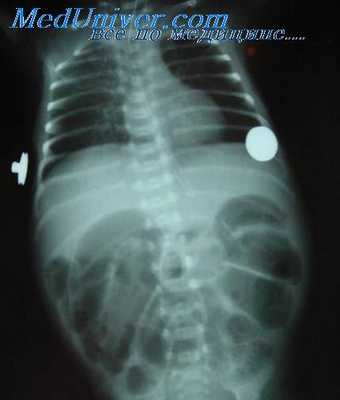

8. Скопление газа и жидкости в кишечнике.

9. Свободный газ и (или) жидкость (кровь) в брюшной полости или забрюшинном пространстве.

Расширение просвета органа часто сочетается со значительным скоплением в нем содержимого, обычно газа и жидкости. Выяснение характера (локальное, диффузное) и причины (стеноз, парез) обнаруженного расширения просвета имеет большое дифференциально-диагностическое значение.